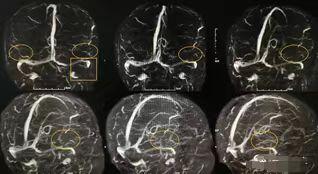

于是进一步完善凝血五项:D-二聚体2.68ng/ml;蛋白C活性:150%(正常值:100.24±17.18)、蛋白S活性:120%(100.9±11.6);颅脑MRV:皮层静脉断续,显影欠佳,左侧Labbe静脉未显影,左侧横窦、乙状窦显影欠佳(图5)。综上,明确患者诊断:颅内静脉系统血栓形成。

图5治疗上,给予患者低分子肝素5100iu皮下注射q12h,稳定斑块、神经保护等综合治疗。出院时,患者精神行为正常,可与家人进行简单沟通。